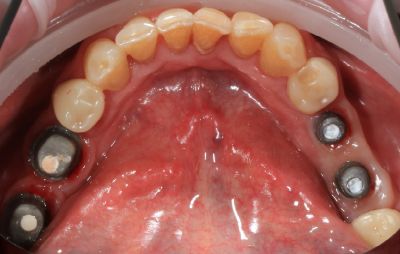

Этап 2. Хирургический этап

Установка имплантатов проводится при использовании специального хирургического шаблона. Этот шаблон позволит хирургу-имплантологу установить имплантаты в челюсть в заранее спланированное место, под абсолютно правильным углом и на заранее определенную глубину с точностью до долей миллиметра.

Во время операции вам устанавливают в челюсть 4,6 либо 8 имплантатов. Если на момент операции в челюсти находятся зубы, подлежащие удалению, то их (непосредственно перед имплантацией) удалят. Далее вы отдыхаете после операции в индивидуальной палате под наблюдением медицинской сестры и врача-анестезиолога, а в это время зубной техник в зуботехнической лаборатории изготавливает вам временный несъемный протез (состоящий из 10-14 искусственных зубов).

Этап 3. фиксация временного протеза

Через 3-5 часов после операции на ваших имплантатах врач зафиксирует временный несъемный протез из высококачественной акриловой пластмассы, и вы сможете покинуть клинику. В течение следующих 10 дней вам будет необходимо 1-2 раза приехать в клинику на повторный осмотр и снятие швов. Практически сразу вы сможете жевать пищу умеренной жесткости, что также ускорит процесс приживляемости имплантатов.